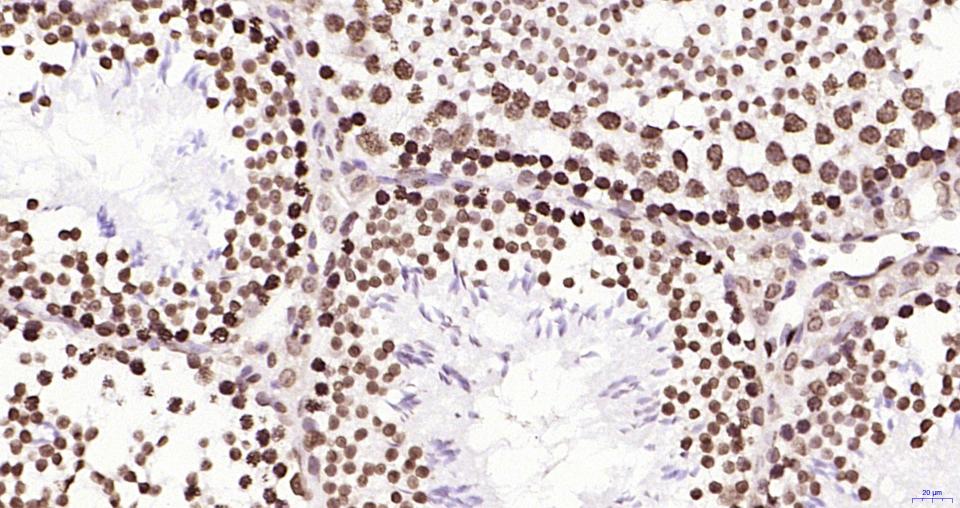

Paraformaldehyde-fixed, paraffin embedded Mouse Testicles; Antigen retrieval by boiling in sodium citrate buffer (pH6.0) for 15 min; Antibody incubation with Histone H2A.X Monoclonal Antibody, Unconjugated(bsm-61080R) at 1:200 overnight at 4°C, followed by conjugation to the SP Kit(Rabbit, SP-0023) and DAB (C-0010) staining.

Paraformaldehyde-fixed, paraffin embedded Rat Testicles; Antigen retrieval by boiling in sodium citrate buffer (pH6.0) for 15 min; Antibody incubation with Histone H2A.X Monoclonal Antibody, Unconjugated(bsm-61080R) at 1:200 overnight at 4°C, followed by conjugation to the SP Kit(Rabbit, SP-0023) and DAB (C-0010) staining.